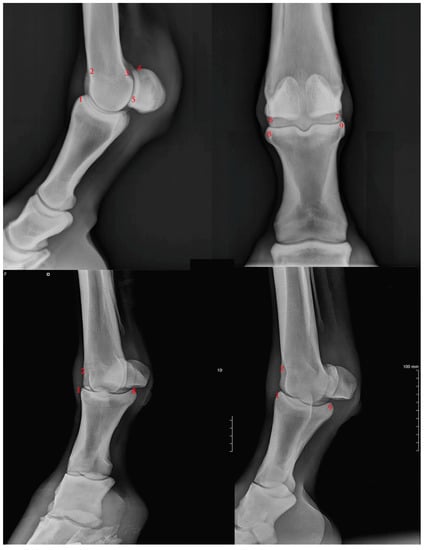

To assess the degree of osteophytosis it was decided to observe the radiographs and issue a judgement focusing on nine anatomical points of the MCP joint, where it is typical to find lesions characteristic of the pathology. These points are described in Figure 1.

Figure 1.

Anatomical assessment point description: 1) P1 dorso-proximal margin; 2) MC3 dorso-proximal margin; 3) caudo-proximal supracondylar margin; 4) PSB proximal margin; 5) PSB distal margin; 6) MC3 lateral margin; 7) MC3 lateral margin; 8) P1 medial margin; 9) P1) lateral margin. P1: 1st phalanx; MC3: 3rd metacarpal bone; PSB: proximal sesamoid bones.